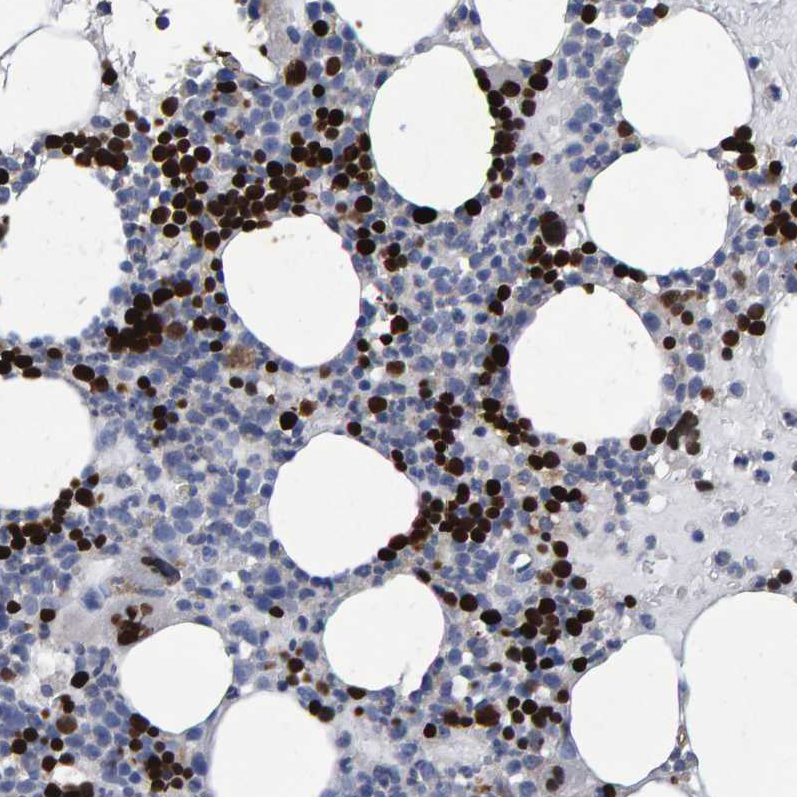

Immunohistochemistry analysis in human bone marrow and cerebral cortex tissues using HPA019572 antibody. Corresponding HEMGN RNA-seq data are presented for the same tissues.